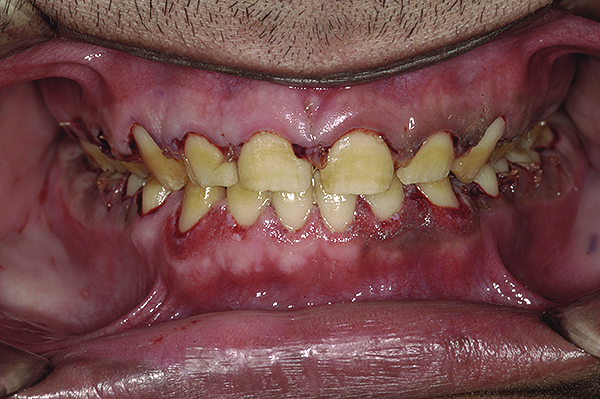

The authors report on a 21-year-old patient who presented with severe discoloration and mild sensitivity of teeth (Figure 1). The teeth visible in his smile were very short, unsightly, and unbecoming for his age.

A thorough clinical examination and analysis were carried out to assess the esthetic and functional problems of the patient (Figure 2 through Figure 7). The medical history was non-contributory, except for mild leukoderma. Temporomandibular joint (TMJ) function was within normal range.

Figure 5. Preoperative 1:1 retracted frontal view.

Figure 5